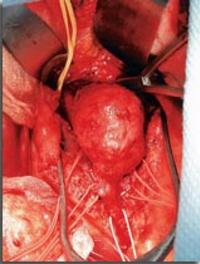

En 2002, l’équipe d’Alain Cribier de Rouen, publiait dans Circulation l’observation du premier patient chez qui avait été pratiqué [...]

Depuis la publication princeps de Charles Dubost en 1951, on peut traiter chirurgicalement les anévrysmes de l’aorte abdominale (AAA). [...]

Depuis maintenant plus d’une décennie, des techniques de réparation endovasculaire (REV) de l’aorte ont été mises au point pour le [...]

La chirurgie a longtemps était réfractaire aux études randomisées. Sans doute pour des raisons méthodologiques (la chirurgie excluant [...]